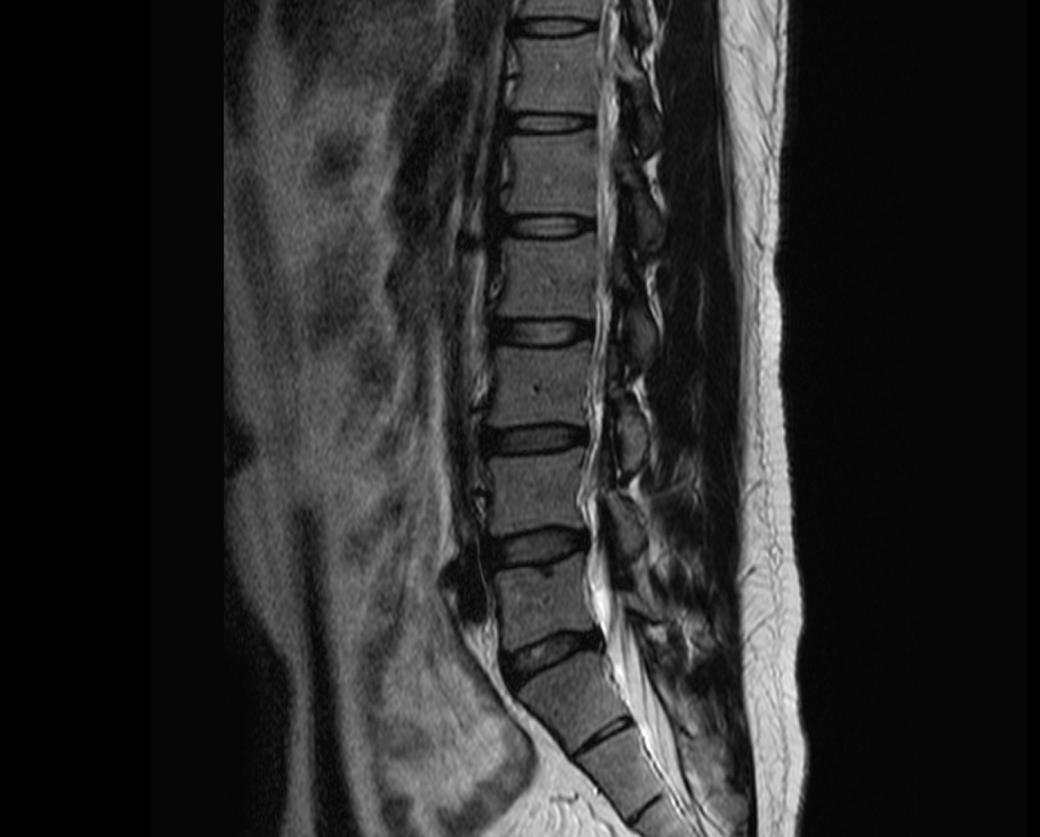

MRI 판독지 및 사진 해석 부탁드립니다.

1년전에 허리가 안좋아서 MRI를 찍었는데 저번주에 경미한 교통사고가 났습니다.

그 후 다리에 저림증상이 있기 시작했고 피가 안통하는 느낌이 들기 시작했습니다.

경미한 교통사고가 다리저림에 원인일 수 있을까요? MRI판독 부탁드립니다 ㅠㅠ

현재

• 4번 째 사진

1년 전 사진에 비해 허리디스크 상황이 악화된 것으로 생각됩니다. 다리저림은 이로 인한 증상으로 생각됩니다.

그러나, 말씀하신 내용과 검사결과만으로는 교통사고와의 연관성에 대해 단정지어 말하기는 어렵습니다. 증상이 점차 악화되어 발생한 것인지, 교통사고에 의해 갑자기 악화된 것인지에 대한 판단이 추가로 필요하겠습니다.